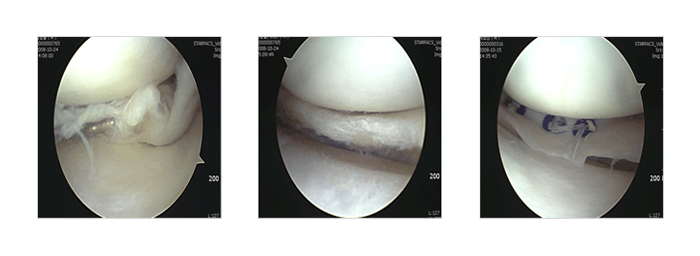

연골판 파열

무릎 위의 뼈 ( 대퇴골 ) 와 아래뼈 ( 경골 ) 사이에서 체중부하시 완충 작용을 하는 조직으로 축구, 스키, 배드민턴, 농구 등 운동시 다치거나 퇴행성 변화 그리고 장기간 무릎에 하중을 주는 반복 동작에서도 파열 될수 있습니다 수술은 크게 부분 절제술과 봉합술 그리고 연골판 이식술로 나누게 되는데 절제와 봉합은 파열의 위치, 형태, 기간, 나이 등을 고려하여 결정하게 되며 모든 파열이 봉합 할 수 있는 것은 아닙니다. 봉합하여 살리는 것이 가장 좋기는 하나 봉합이 어려운 형태는 기술적으로 가장 적은 양을 절제하고 많은 양을 남기는 것이 중요합니다. 연골판 이식은 파열이 너무 심하거나 수차례 절제하여 연골판을 보존 할수 없을 때 타인의 연골판을 이식하는 것입니다.

연골판 파열 - 사진